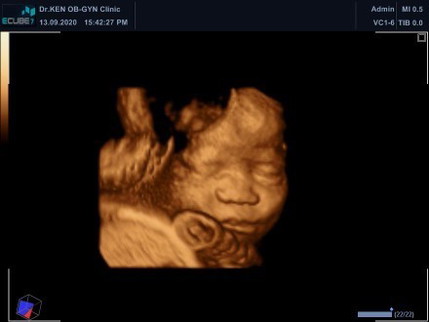

แม่ๆที่อายุครรภ์8เดือน นน.น้องเท่าไหร่กันบ้างแล้วคะบ้านนี้1930น้อยไปมั้ยคะ